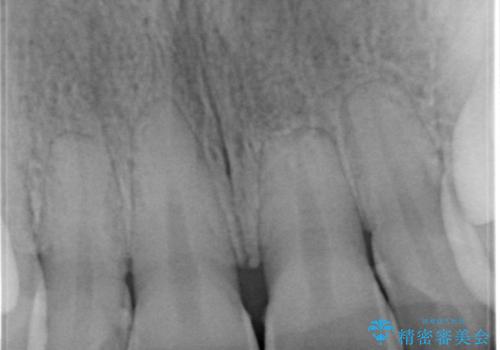

- 前歯の色が気になるとのことでご相談にいらした患者様です。診断の結果、前歯は2本とも失活していたために精密根管治療から治療を開始しました。根管治療後にウォーキングブリーチを行うことで歯の色をトーンアップさせました。患者様より周囲の歯も全体的に白くしたいとのご希望があったため、オフィスホワイトニングも併せて行いました。

ウォーキングブリーチ法とは歯の中に薬剤を入れて内側からホワイトニングを行う方法であるため、根管治療がされている歯のみ適応となります。生活歯(神経が生きている歯)に対してはオフィスホワイトニングやホームホワイトニングが有効です。